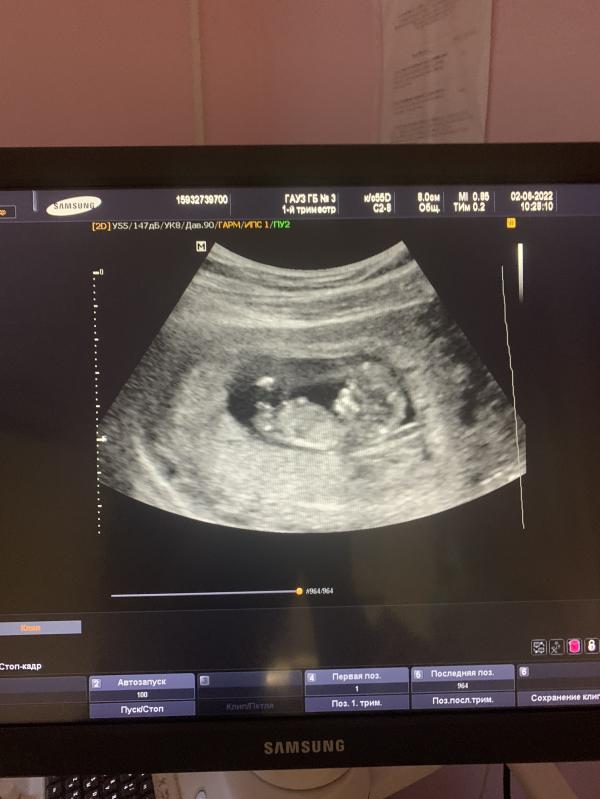

Сегодня был первый скрининг (НАКОНЕЦ-ТО!!!)

По узи все хорошо, но пол конечно же не сказали( жду анализы крови, надеюсь, там тоже все идеально 🥰

Девочки, на каком сроке на узи будет виден пол малыша? Хочет уже узнать кто там и называть по имени ☺️